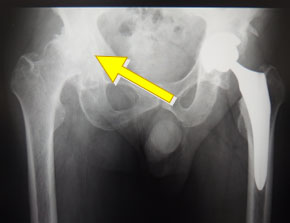

⑤転んだあと、右ひざが痛くて歩いて来院→大腿骨頚部骨折(下図)

⑥右ひざが痛くて歩きづらい→変形性股関節症(下図)